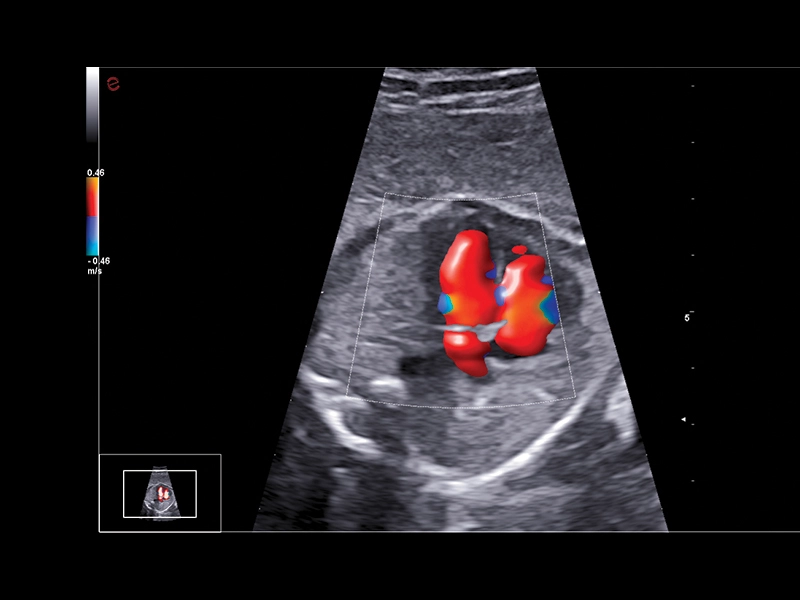

B-mode/M-Mode/CFM/Doppler/Power Doppler/microV

HD Color Doppler (CFM) i Power Doppler (PDI) kao i Directional Power Doppler (DPDI) sa visokom osetljivošću i definicijom.

XFlow, MicroV i MicroV HFR za povećanje osetljivosti i rezolucije u snimanju protoka krvi

BrightFlow – 3D kolor efekat

KLINIČKE SLIKE